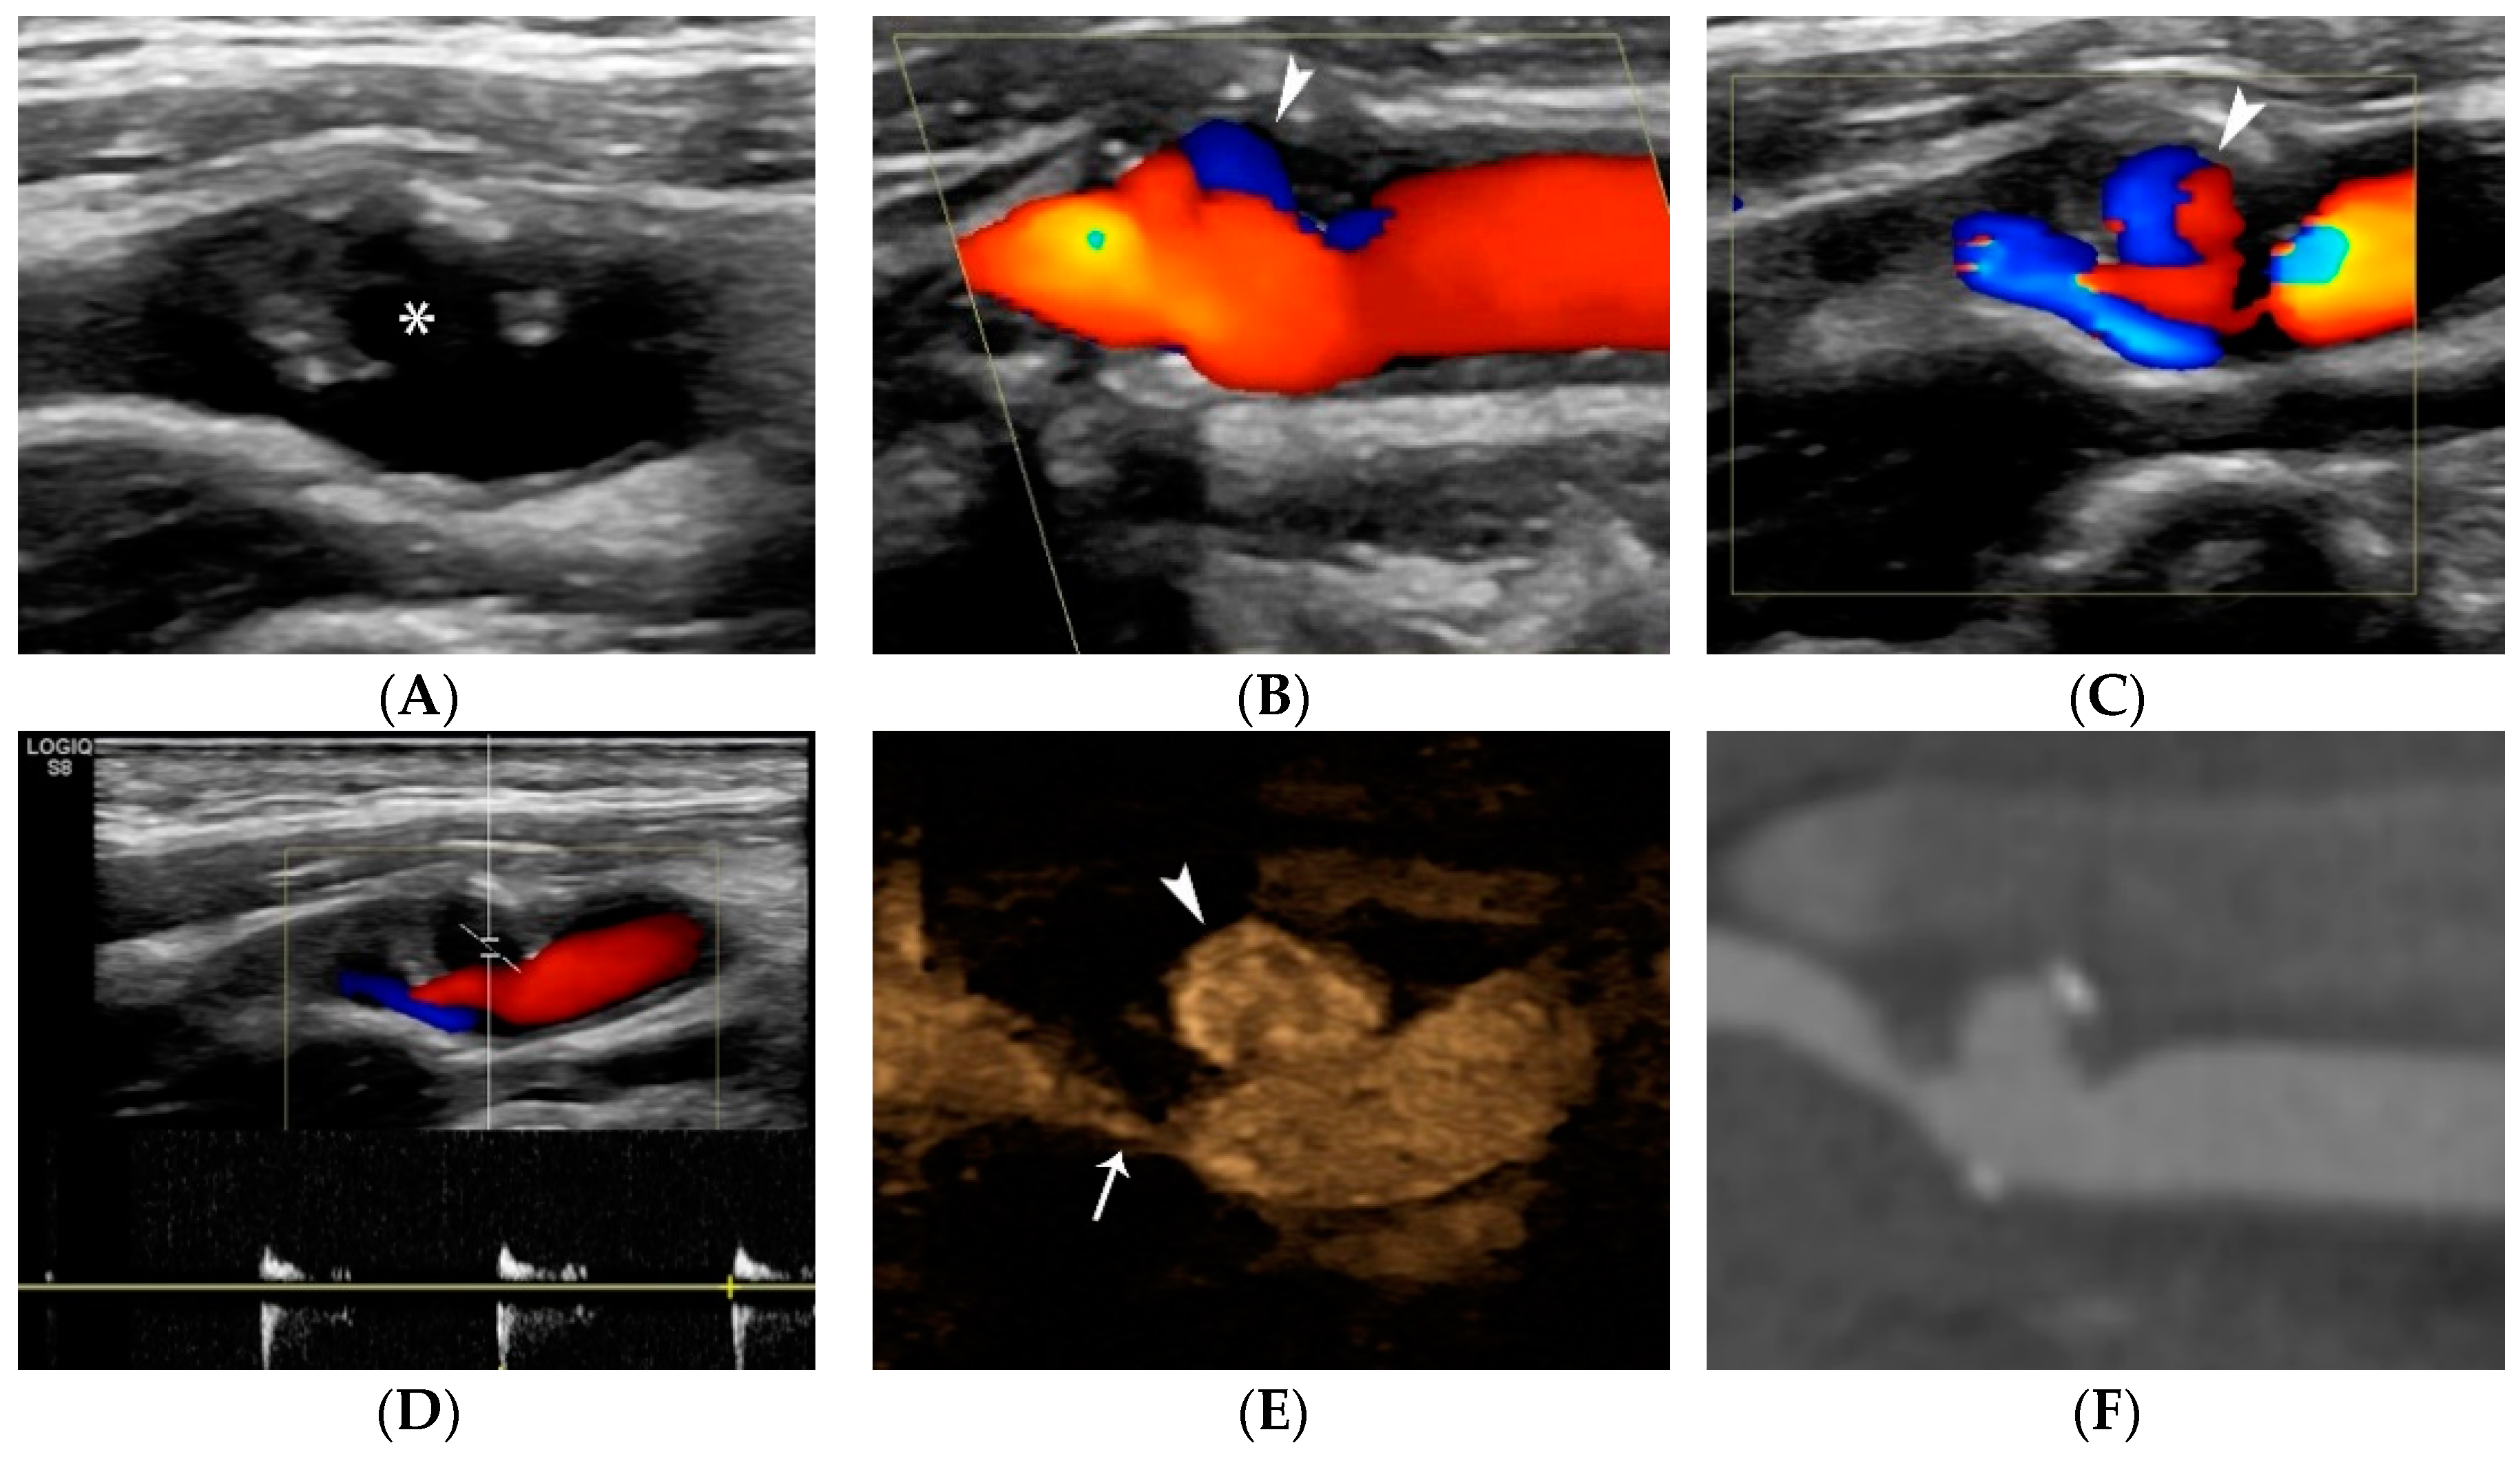

4.1.4. Plaque Ulceration

- Rafailidis, V.; Chryssogonidis, I.; Tegos, T.; Kouskouras, K.; Charitanti-Kouridou, A. Imaging of the ulcerated carotid atherosclerotic plaque: A review of the literature. Insights Imaging 2017, 8, 213–225. [Google Scholar] [CrossRef]

- Hamada, O.; Sakata, N.; Ogata, T.; Shimada, H.; Inoue, T. Contrast-enhanced ultrasonography for detecting histological carotid plaque rupture: Quantitative analysis of ulcer. Int. J. Stroke 2016, 11, 791–798. [Google Scholar] [CrossRef] [PubMed]

- ten Kate, G.L.; van Dijk, A.C.; van den Oord, S.C.; Hussain, B.; Verhagen, H.J.; Sijbrands, E.J.; van der Steen, A.F.; van der Lugt, A.; Schinkel, A.F. Usefulness of contrast-enhanced ultrasound for detection of carotid plaque ulceration in patients with symptomatic carotid atherosclerosis. Am. J. Cardiol. 2013, 112, 292–298. [Google Scholar] [CrossRef] [PubMed]

- Rafailidis, V.; Charitanti, A.; Tegos, T.; Rafailidis, D.; Chryssogonidis, I. Swirling of microbubbles: Demonstration of a new finding of carotid plaque ulceration on contrast-enhanced ultrasound explaining the arterio-arterial embolism mechanism. Clin. Hemorheol. Microcirc. 2016, 64, 245–250. [Google Scholar] [CrossRef]

- Rafailidis, V.; Chryssogonidis, I.; Xerras, C.; Nikolaou, I.; Tegos, T.; Kouskouras, K.; Rafailidis, D.; Charitanti-Kouridou, A. A comparative study of color Doppler imaging and contrast-enhanced ultrasound for the detection of ulceration in patients with carotid atherosclerotic disease. Eur. Radiol. 2019, 29, 2137–2145. [Google Scholar] [CrossRef]

- Lyu, Q.; Tian, X.; Ding, Y.; Yan, Y.; Huang, Y.; Zhou, P.; Hui, P. Evaluation of Carotid Plaque Rupture and Neovascularization by Contrast-Enhanced Ultrasound Imaging: An Exploratory Study Based on Histopathology. Transl. Stroke Res. 2021, 12, 49–56. [Google Scholar] [CrossRef]